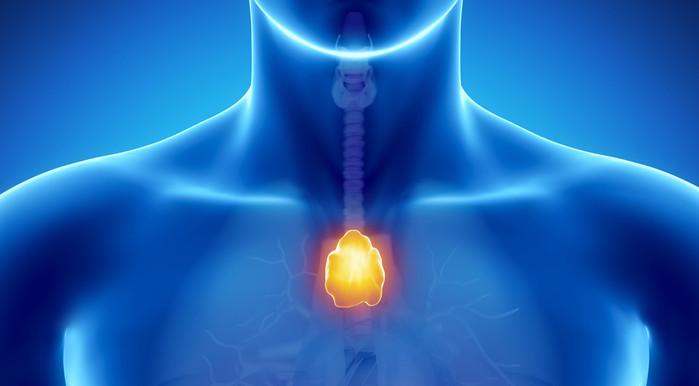

흉골 뒤쪽에 있는 흉선은 신생아와 어린이의 면역 체계를 훈련시키는 중요한 기관이다. 이 기관에서 T 세포가 성숙해 신체의 세포와 조직을 침입하는 병원균이나 병리학적 변화와 구별하는 법을 배운다. 또한, 자연 살해 세포(NK 세포)도 흉선에서 생성된다는 사실이 2025년에 밝혀졌다.

성인의 경우, 흉선은 오랫동안 불필요한 기관으로 여겨져 왔다. 면역 기관인 흉선은 나이가 들면서 위축되고, 그 기능에 필요한 조직은 지방 조직으로 변한다. 하지만 2023년 연구에 따르면 흉선을 제거한 사람들은 암 발생 위험과 조기 사망 위험이 현저히 높은 것으로 나타났다.

가슴에 위치한 흉선의 상태는 암, 심혈관 질환 및 사망 위험에 영향을 미친다. 미국에서 진행된 대규모 연구에 따르면, 성인의 흉선이 크고 기능이 좋을수록 이러한 질병 발생 위험이 낮아지는 것으로 나타났다. 또한, 연구진은 "네이처(Nature)"지에 발표한 연구 결과를 통해 흉선 상태가 암에 대한 면역요법의 성공률에도 영향을 미칠 수 있다고 보고했다.

| ▲ 가슴뼈 뒤쪽에 위치한 흉선은 오랫동안 성인에게는 기능이 없고 불필요한 기관으로 여겨졌다. 하지만 이는 잘못된 생각이다. © janulla/ Getty images |

흉골 뒤쪽에 있는 흉선은 신생아와 어린이의 면역 체계를 훈련시키는 중요한 기관이다. 이 기관에서 T 세포가 성숙해 신체의 세포와 조직을 침입하는 병원균이나 병리학적 변화와 구별하는 법을 배운다. 또한, 자연 살해 세포(NK 세포)도 흉선에서 생성된다는 사실이 2025년에 밝혀졌다.

성인의 경우, 흉선은 오랫동안 불필요한 기관으로 여겨져 왔다. 면역 기관인 흉선은 나이가 들면서 위축되고, 그 기능에 필요한 조직은 지방 조직으로 변한다. 하지만 2023년 연구에 따르면 흉선을 제거한 사람들은 암 발생 위험과 조기 사망 위험이 현저히 높은 것으로 나타났다.